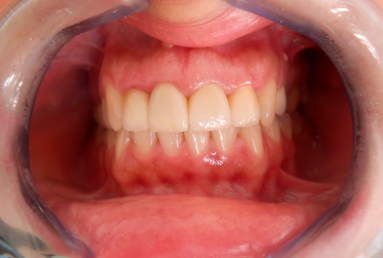

Before treatment: three porcelain fused to metal crowns on the right lateral incisor and on the two central incisors, left lateral incisor has a big composite filling and an old root canal treatment. The patient will receive full ceramic crowns on all four upper incisors.